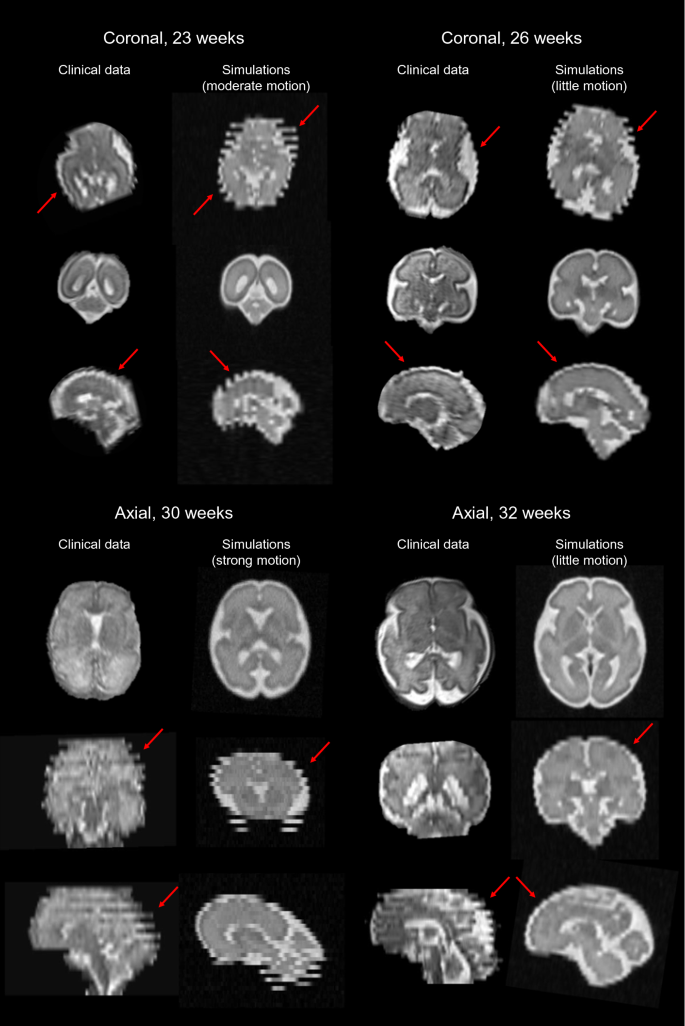

Figure 2 illustrates the close resemblance between simulated HASTE images of the fetal brain and clinical MR acquisitions in terms of MR contrast between tissues, SNR, brain anatomy and relative proportions across development for representative subjects in the GA range of 23 to 32 weeks, as well as typical out-of-plane motion patterns related to the interleaved slice acquisition scheme. A neuroradiologist and a pediatric (neuro)radiologist report a good contrast between gray and white matter, which is important to investigate the cortex continuity and identify the deep gray nuclei as well as any neuronal migration defect. The radiologists also notice good SNR in the different series and report proper visualization of the main anatomical structures: the four ventricles, the corpus callosum, the vermis, the cerebellum, even sometimes the fornix. Besides, the experts are able to monitor the evolution of normal gyration throughout gestation. However, the radiologists point out that small structures such as the pituitary gland, the chiasma, the recesses of the third ventricle, and the vermis folds that look part of the cerebellum, are more difficult to observe. The cortical ribbon is clearly visible but quite pixelated, which is likely to complicate the diagnosis of polymicrogyria. White matter appears too homogeneous, which makes its multilayer aspect barely distinguishable, with an MR signal that is constant across GA, thus preventing physicians from exploring the myelination process throughout brain maturation.

Visual inspection and comparison between clinical MR acquisitions and representative simulated HASTE images of the fetal brain in the three orthogonal orientations at four different GA (23, 26, 30 and 32 weeks). The amplitude of movement of the fetus is indicated from the motion index computation. Red arrows point out typical out-of-plane motion patterns.